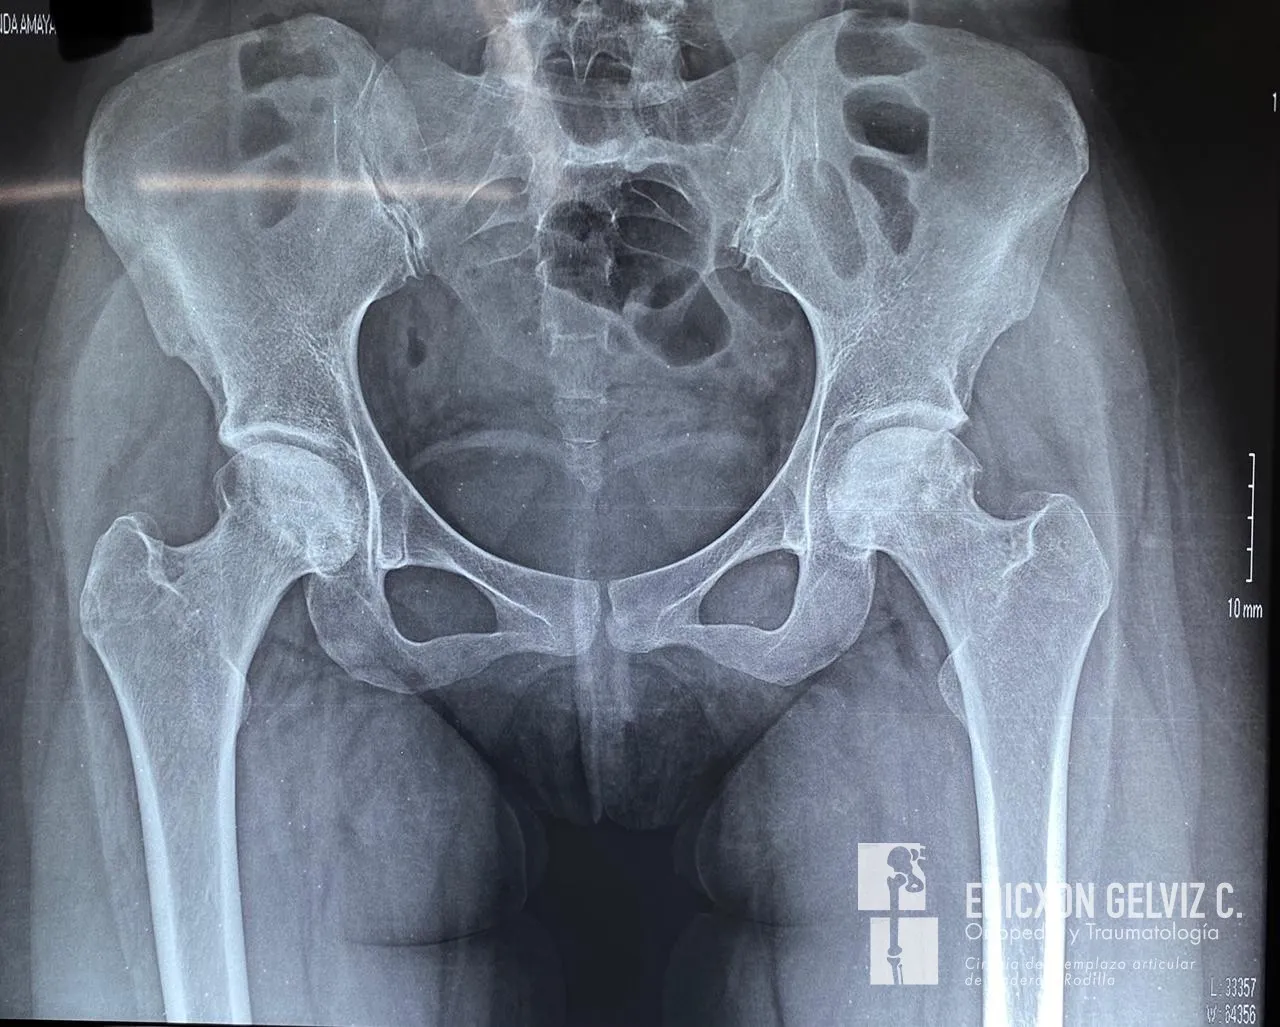

Las radiografías preoperatorias muestran el estado de deterioro articular en ambas caderas. Se evidencia pérdida del espacio articular, deformidad de las cabezas femorales y cambios degenerativos avanzados, inusuales para una paciente tan joven.

Radiografía preoperatoria de pelvis AP mostrando coxartrosis bilateral severa en paciente de 25 años

Radiografía preoperatoria de pelvis AP: se observa coxartrosis bilateral severa con pérdida del espacio articular en ambas caderas.